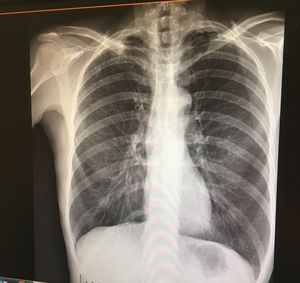

Anything wrong with this X-ray?

COPD

Chronic Obstructive Pulmonary Disease

Hyperinflation, flat diaphragm = COPD

Kerley striae, cardiac failure?

Kerley lines and boot heart - chf?

Maybe lung cancer or COPD which affected right lung mostly and why the heart is shrunken??

What Is That Black Shadow In The Bottom Right Of The Picture?

It’s called fundic bubble

It is air in the stomach, a usual finding, actually useful to help you locate the patient’s left and right.